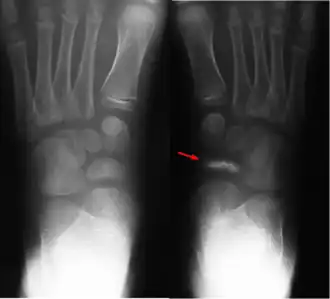

Болезнь Кёллера I — хроническое дистрофическое заболевание ладьевидной кости стопы, приводящее к её асептическому некрозу.

Причина асептического некроза у детей объясняется нарушением процесса окостенения ладьевидной кости. Что подтверждается на рентгенограммах: отмечается сплющивание, фрагментизация ядра окостенения, увеличение межкостного пространства, отделяющего ладьевидную кость от таранной и клиновидной.